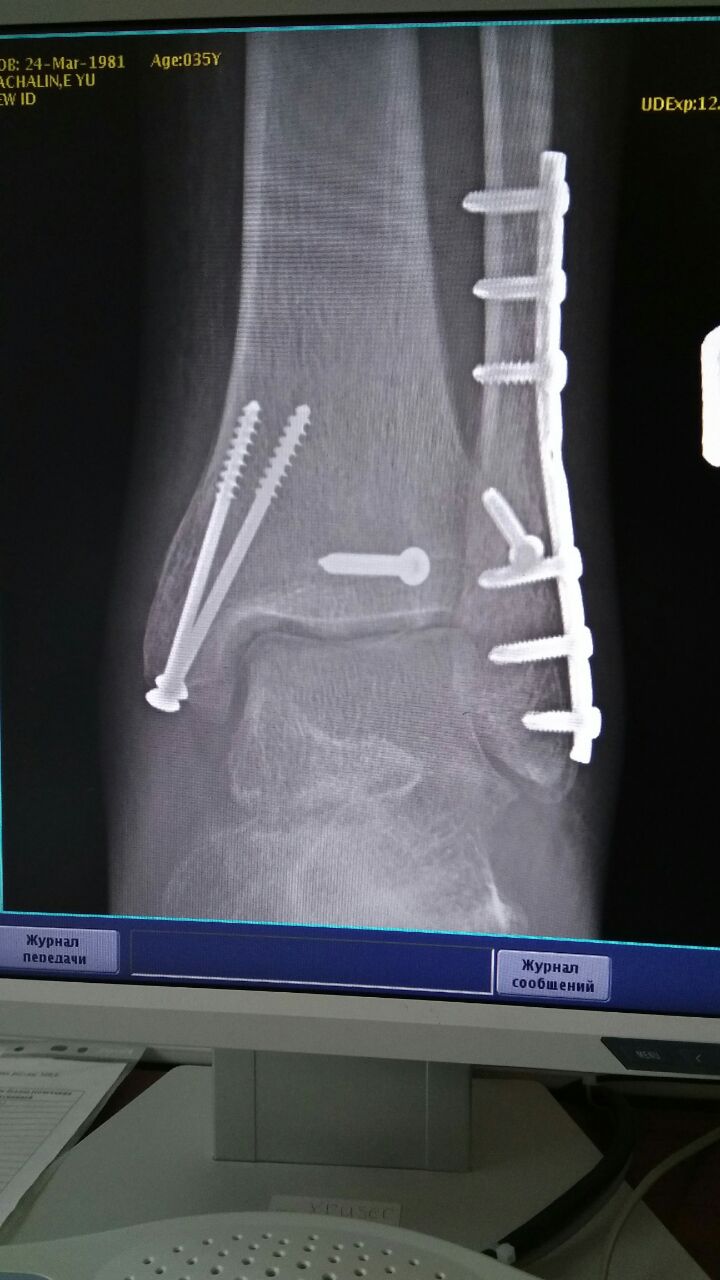

Когда травма была? Скинь рентген снимки до операции и после операцит

Скинь снимки и даты травмы,операции и выписки

Eugene

Травма 9.11.2016, операция 24.11.2016

Артроз у тебя будет, это факт

Собрали в принципе неплохо

Для твоего перелома